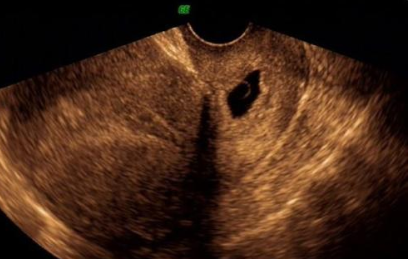

宮頸妊娠是一種異位妊娠,很多時候如果出現(xiàn)宮頸妊娠,對胎兒和母體本身的健康影響是很大的,那么宮頸妊娠藥物怎么治療 宮頸妊娠是大手術(shù)嗎。下面八寶網(wǎng)的小編就來介紹。

依據(jù)宮頸妊娠屬于異位妊娠的范疇,因此,治療異位妊娠的藥物和方案都可應(yīng)用于宮頸妊娠患者。甲氨蝶呤(MTX)是一種常用的抗腫瘤藥物,是治療異位妊娠的藥物治療中的首選,可以全身用藥和局部用藥,包括超聲引導(dǎo)下給藥。MTX通過特異性干擾核酸生物合成,阻止細胞的分裂繁殖,同時聯(lián)合米非司酮、中藥口服殺胚起到治療的作用。局部用藥:MTX小劑量局部注射同時聯(lián)合米非司酮、中藥口服后配合清宮術(shù),可獲得較好的治療效果,但推薦用于孕12周內(nèi),血hCG低于10 kU/L者。

宮頸妊娠在早期明確診斷后,常需聯(lián)合藥物、宮頸局部壓迫填塞、環(huán)扎或雙側(cè)髂內(nèi)動脈結(jié)扎、子宮動脈介入栓塞等方法后采用清宮術(shù)治療。對于急性出血者,清宮術(shù)雖能夠快速止血,但對宮腔操作技巧要求較高,術(shù)中大出血率高。因此,對于病情穩(wěn)定患者,可以行宮腔鏡下清宮治療。宮腔鏡手術(shù)具有直視、無痛、微創(chuàng)的特點,可準確定位、清除妊娠組織,并電凝止血達到治療的目的,保留了宮頸的完整性。近年來有報道,先在腹腔鏡下結(jié)扎子宮動脈,再行宮腔鏡切除妊娠組織治療取得滿意的療效。但是即使進行了系列預(yù)處理,難以控制的大出血仍可能發(fā)生。因此,術(shù)前需建立靜脈通道、做好輸血及其他搶救準備,術(shù)中局部注射稀釋的血管加壓素或垂體后葉素,同時操作需輕柔、術(shù)中監(jiān)測患者病情,術(shù)后使用紗布局部填塞或Foley 尿管壓迫止血,可以降低子宮切除率至15%。目前,對于局部止血方法也在改進,如雙腔球囊管“三明治”式壓迫止血,雙側(cè)子宮動脈臨時阻斷,可減少術(shù)中出血,改善患者預(yù)后。